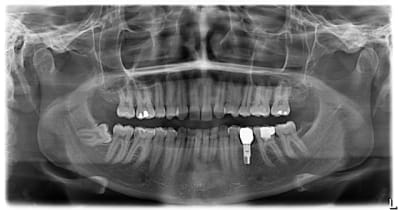

37 semble aussi abrasée, donc je soupconne une abrasion et des parafonctions

couronne CAO

Je ne vois pas en quoi l'usure provoquée de 36 et l'usure soupçonnée sur 37 seraient des contre-indications . Tant qu'à avoir peur , l'implant lui même avec un problème occlusal général et des dysfonctions...ouin .

Peut-être la cause de la perte de la 35 , (mais c'est probablement une agénésie) pourrait donner une réponse et orienter le choix de protection totale et le choix invasif d'emblée de la 36 . Je trouve étonnant que l'espace (35) soit intact , tu nous diras si tu as fait de l'ortho pour regagner l'espace et l'historique du secteur 3 .

Mais il y a fort à parier au regard de la courbure importante de la racine mésiale qu'il faudra élargir cette chambre en mésiale, à ceci s'ajoute une carie débutante toujours en mésiale (sans parler des caries multiples un peu partout), donc on se dirige à mon avis vers de la prothèse périphérique.

Par contre le titre dit "bio et ensuite", ben ensuite, c'est soins conservateur multiples (y a du boulot), motivation hygiène (c'est bizarre toutes ces caries dans une bouche présentant un implant, signe de patient généralement motivé!), et enfin CCC.

patiente 26 ans,

effectivement implant 35 suite à la perte de la 75 tardivement ( agénésie de la 35 )

rien avoir avec le sujet, mais au niveau de la 48 vous laissez tel quel dans la theorie ?

Moi non, et encore moins depuis que je ne sais plus qui a posté une panoramique sur eugenol montrant clairement les racines des 7 en train de se faire dévorer toute crues (il me semble même que la 37 était limite en pulpite à cause de ça)